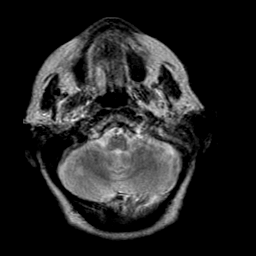

Creutzfeld-Jakob disease: T2-weighted MR -- Slice #3

[Home][Help][Clinical] Slice 3